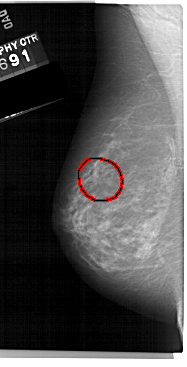

A_1224_1.LEFT_MLO

LEFT_MLO LINES 5491 PIXELS_PER_LINE 2791 BITS_PER_PIXEL 12 RESOLUTION 43.5 OVERLAY

FILE: A_1224_1.LEFT_MLO.OVERLAY

TOTAL_ABNORMALITIES 1

ABNORMALITY 1

LESION_TYPE MASS SHAPE IRREGULAR MARGINS SPICULATED

ASSESSMENT 4

SUBTLETY 3

PATHOLOGY MALIGNANT

TOTAL_OUTLINES 1

BOUNDARY